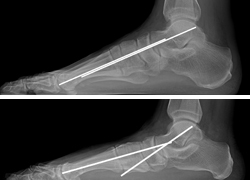

Un pie plano rígido puede requerir que el hueso del talón sea realineado y fusionado debajo del hueso del tobillo. Para corregir la forma del arco en sí, es posible que también se deban fusionar los huesos de la parte interna del pie.

En esta radiografía, se observa una deformidad por pie plano con mucha rigidez. Se necesita una fusión de las tres articulaciones en la parte posterior del pie, con la que se puede recrear con éxito el arco y permite restaurar la función.